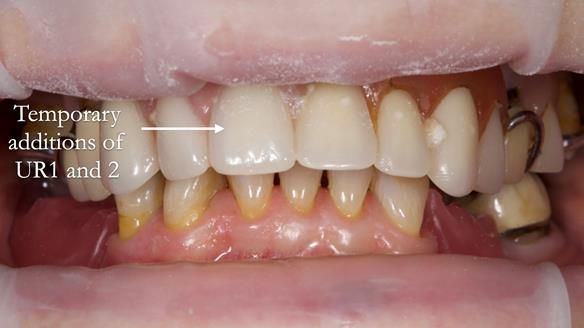

- Add upper right lateral and central incisor denture teeth to existing upper RPD as temporary measure during making of new RPDs

- The upper right central and lateral incisors with post crowns. Healthy and functionally secure but with poor appearance, contributing to the reverse curve.